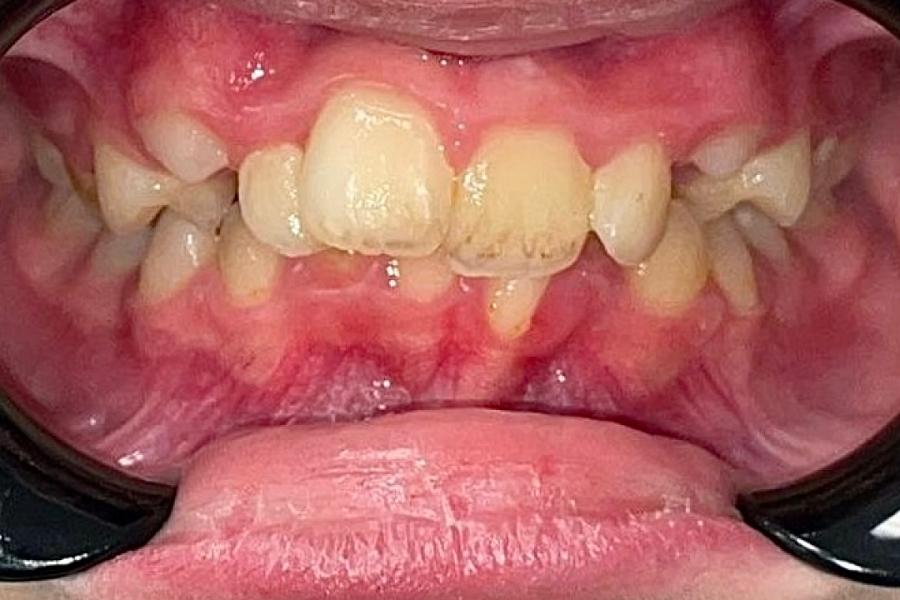

Пациентке 9 лет. Имеется ряд проблем:

- ротация верхней челюсти

- скученное положение зубов

- глубокая окклюзия

Изменения отлично видны на фото: положение зубов значительно изменилось. Зубки теперь растут ровными рядами.